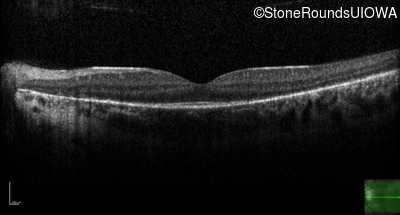

Optical Coherence Tomography - Left - 20/20 sc

Exemplar / OCT Stack

OCT Stack